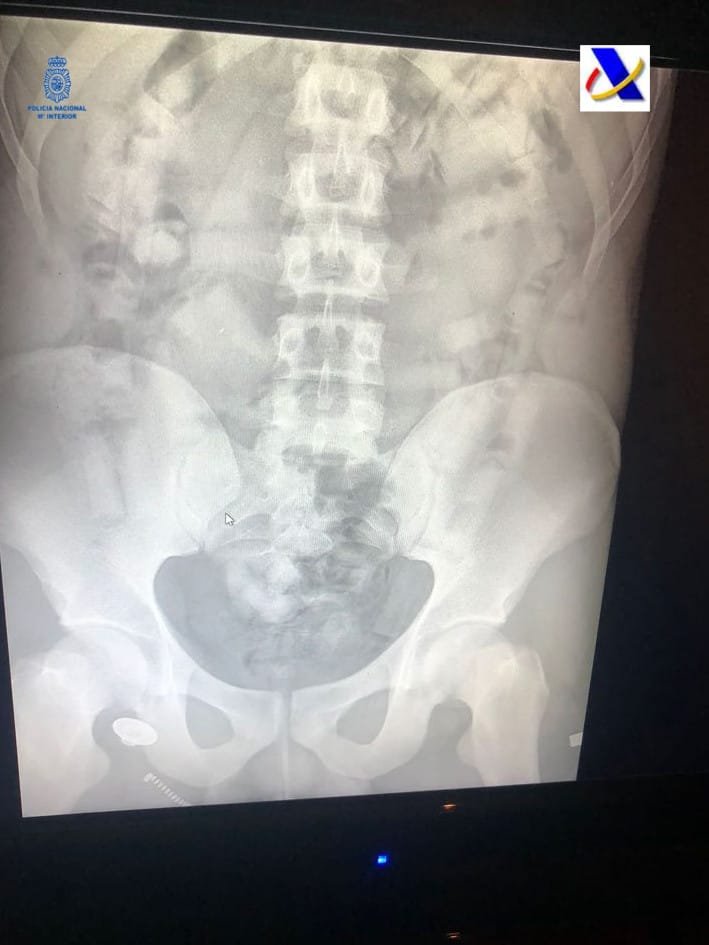

Con motivo de un control en uno de los vuelos llegado de Sudamérica fue detenido un varón del que los policías sospecharon pudiera ser portador de sustancias estupefacientes como «mulero» (persona que se introduce en su interior ese tipo de sustancias para una vez salvados los controles preceptivos defecarla y entregarla a su destinatario).

Solicitada la colaboración del servicio de vigilancia aduanera aeroportuario y su sistema de rayos x se pudo confirmar la sospecha anterior. Una vez detenido el viajero e ingresado en el hospital fue expulsando hasta un total de 50 cilindros conteniendo al parecer cocaína, resultando un total de cerca de 400 gramos.